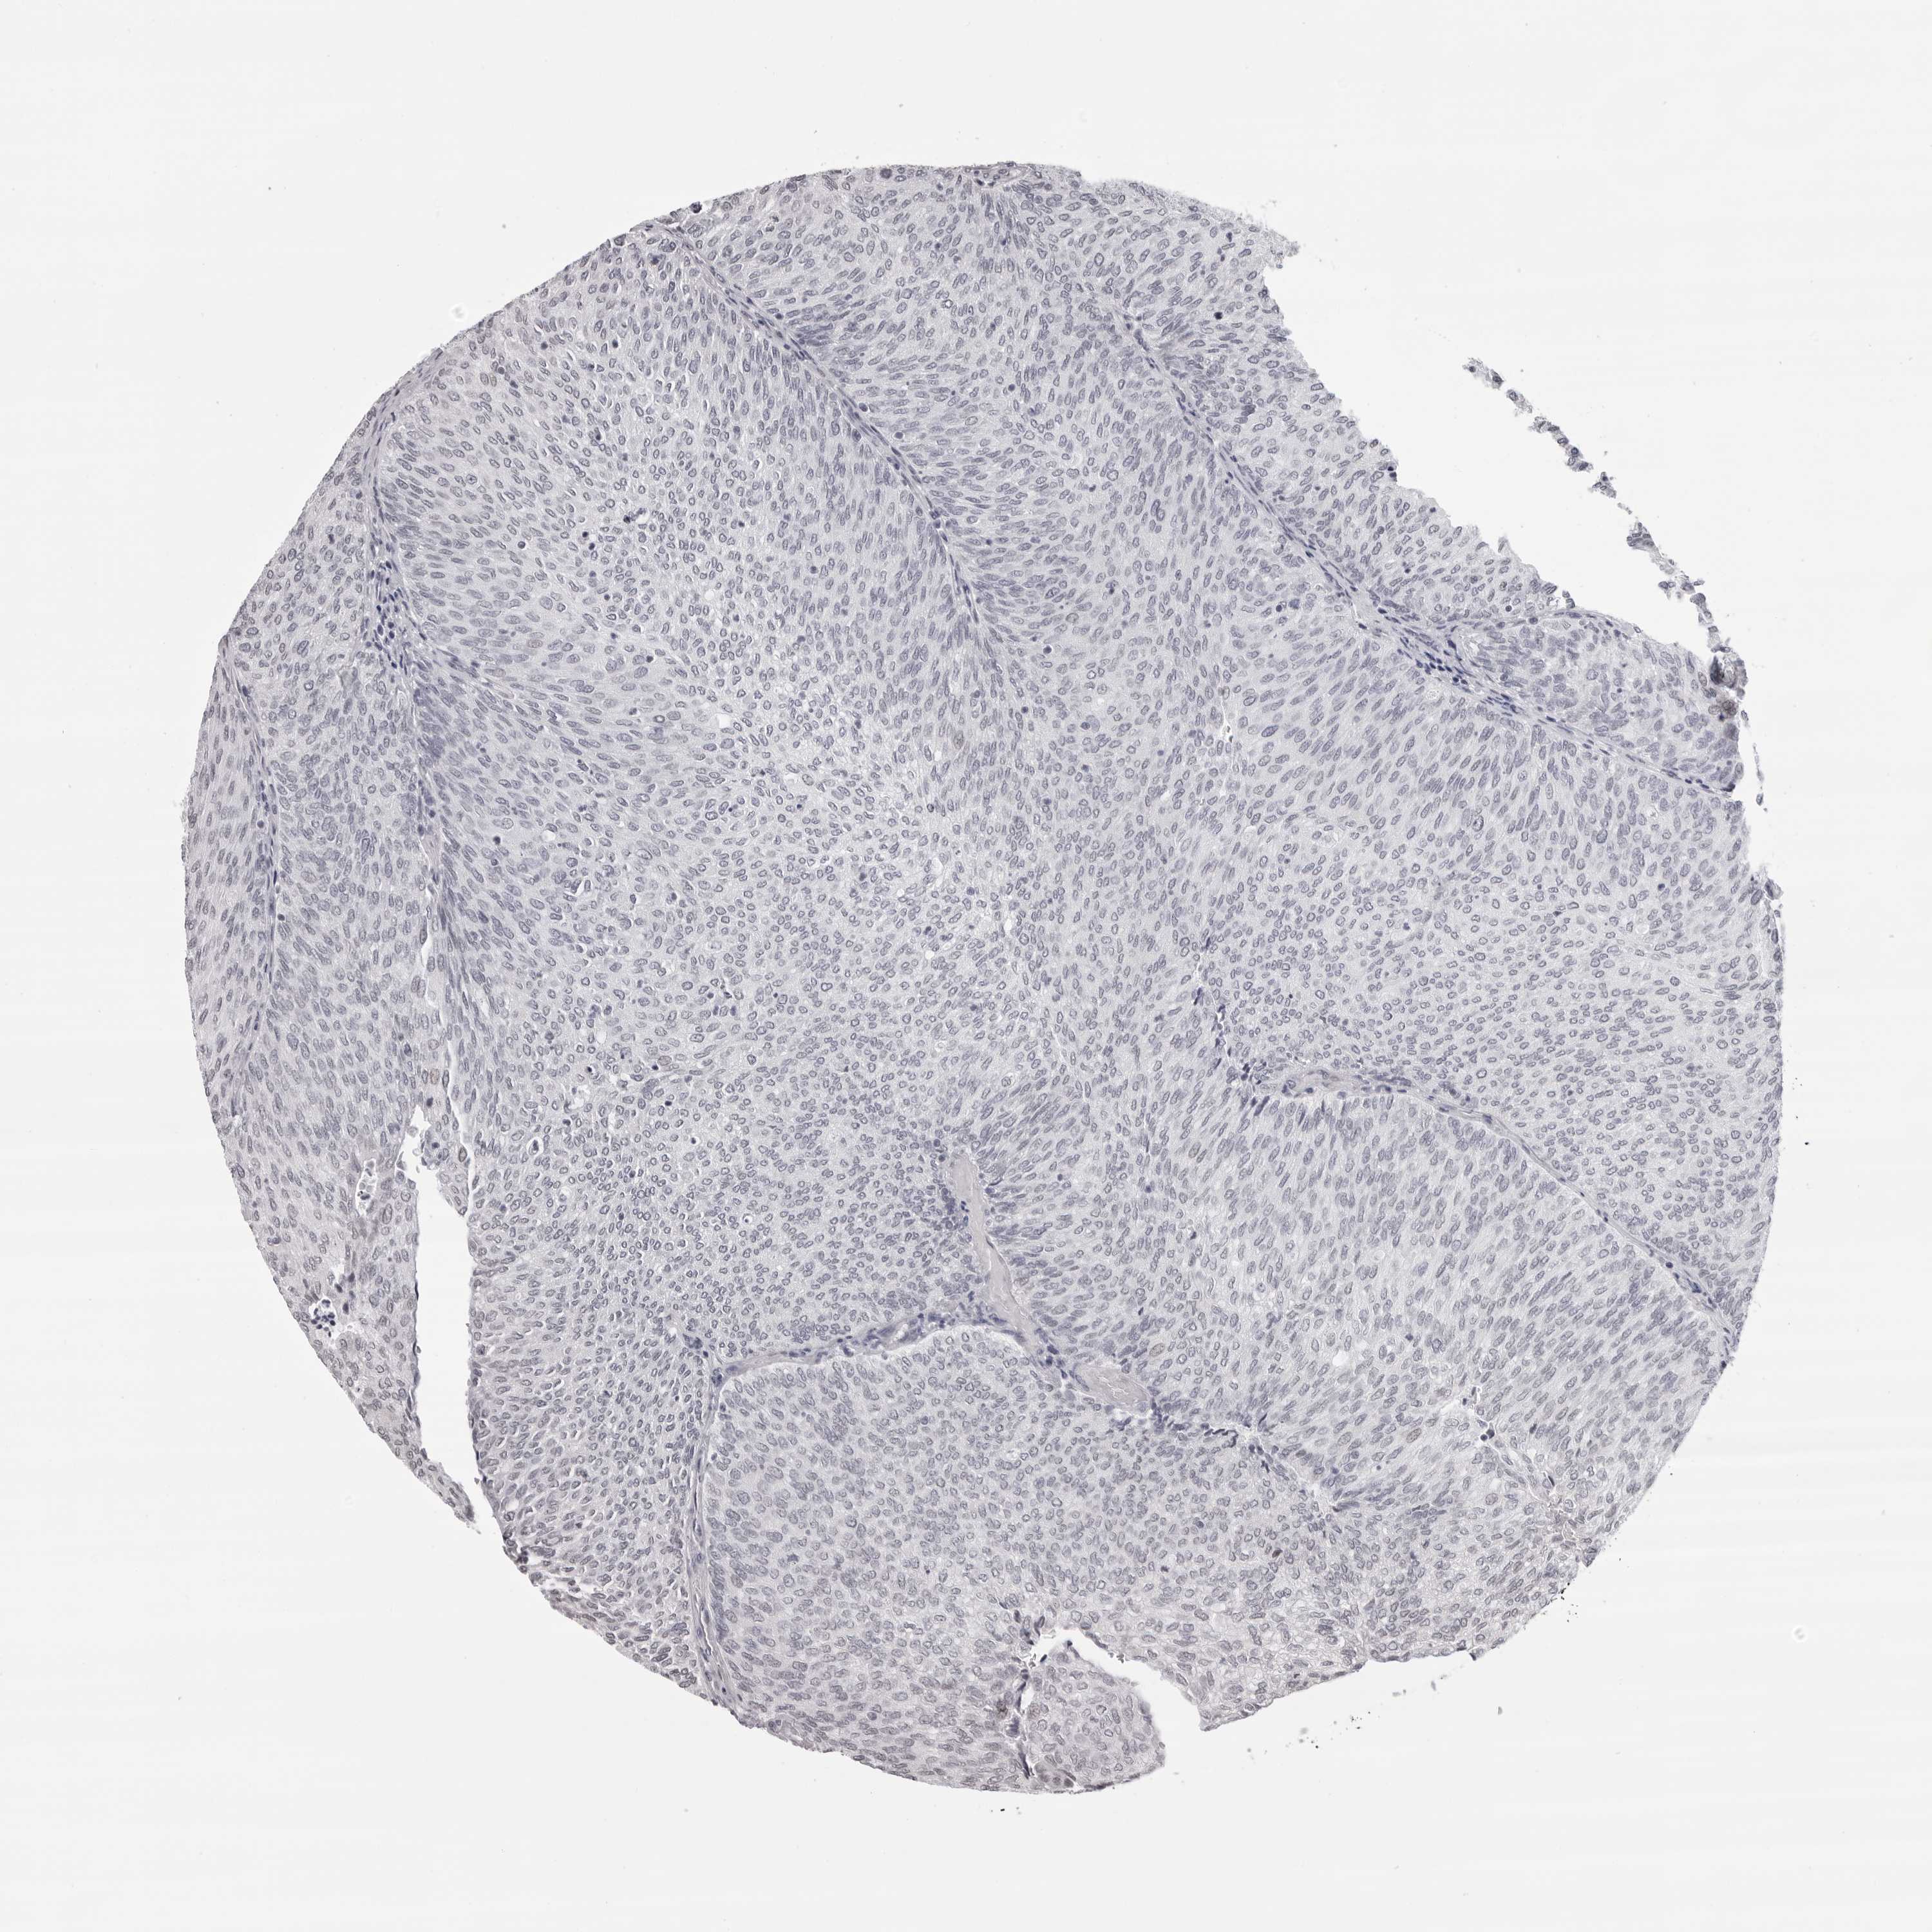

UROTHELIAL CANCER - Protein expressioni

A mouse-over function shows sample information and annotation data. Click on an image to view it in a full screen mode. Samples can be filtered based on level of antibody staining by selecting one or several of the following categories: high, medium, low and not detected. The assay and annotation is described here.

Antibody stainingi

Antibody staining in the annotated cell types in the current human tissue is reported as not detected, low, medium, or high, based on conventional immunohistochemistry profiling in selected tissues. This score is based on the combination of the staining intensity and fraction of stained cells.

Each image is clickable and will lead to virtual microscopy that enables deeper exploration of all samples and also displays staining intensity scores, fraction scores and subcellular localization as well as patient and tissue information for each sample.

Antibody HPA024676

Antibody HPA025763

Staining

High

Medium

Low

Not detected

Intensity

Strong

Moderate

Weak

Negative

Quantity

>75%

75%-25%

<25%

None

Location

Nuclear

Cytoplasmic/membranous

Cytoplasmic/membranous,nuclear

Urothelial carcinoma, Low grade